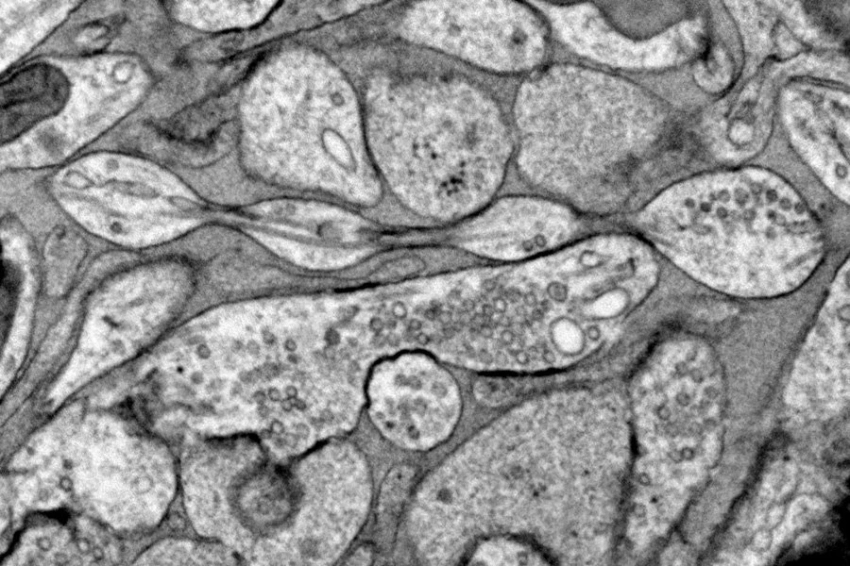

Регулярный просмотр подобных роликов активирует хабенулу. Эта область в человеческом мозге ответственна за чувство удовлетворения и мотивацию. Ученые в ходе эксперимента выяснили, что хабенула может порой отключать способность человека к самоконтролю. И пользователь начинает бесконечно пролистывать ленту, возникает своего рода зависимость от TikTok и схожих платформ.